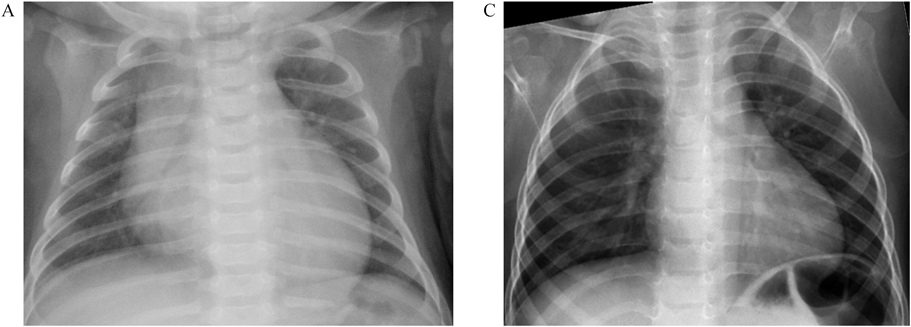

心筋症の予後については,早期死亡が見られる一方で,成長とともに心機能が改善していくことが報告されている.Kangらは,英国の27人のBarth症候群患者について,臨床症状と心臓超音波所見の推移を報告した41).これによると,27人中25人が診断当初より心筋症を有しており,22人は生後6か月以内に診断されていた.27人中,22人が生存し,5人が0.02~4.22歳(1.8歳)で心不全に起因して死亡した.生存例の2.0~22歳(中央値12.6歳)までの心臓超音波検査による経過観察では,心筋ストレイン解析において異常が残存するものの,多くの症例で心機能は3歳以降に改善し,拡張末期径,左室内径短縮率,左室拡張末期圧指標E/E’は正常化した.フランスにおける22症例の研究では,22人中11人が死亡していたが,2000年以前の出生では生存率が20%であったのに対し,2000年以降の出生では生存率が80%に改善し,心機能は同様に3歳以降改善していくことが示された15, 42)Fig. 2に自験例の治療経過を提示した.2か月時に哺乳力低下と体重増加不良を契機に発見され,入院時,胸部X線では心胸郭比65%の心拡大と軽度の肺うっ血を認め(Fig. 2A),BNP値は725 pg/mLと上昇し,心臓超音波検査では左室心筋緻密化障害の所見と心拡大,収縮力低下,中等度の僧帽弁閉鎖不全を認めた(Fig. 2B).βブロッカー,アンジオテンシン変換酵素阻害薬,利尿薬による治療により,1歳過ぎには心拡大は消失し(Fig. 2C)BNPは正常化した.7歳時においても心機能は良好に保たれ,心臓超音波検査では左室心筋緻密化障害の所見と少量の僧帽弁閉鎖不全は認めるものの,心収縮力は良好に保たれている(Fig. 2D).本疾患における心筋障害は,呼吸器感染症などを契機に発見されることもあり,このような心筋障害の回復に加え,好中球減少が感染による骨髄抑制と考えられてしまうことで,ウイルス性心筋炎/心筋症と誤診されることが示唆されている15)

Fig. 2 Imaging findings in a case of Barth syndrome

Chest roentgenogram at the age of 2 months revealing cardiomegaly with a cardiac ratio of 65% and mild pulmonary edema (Fig. 2A). Echocardiogram demonstrating left ventricular noncompaction, left ventricular dilation with LVIDD of 29 mm, poor contractility with LVFS of 13%, and moderate mitral regurgitation (Fig. 2B; movie). Chest roentgenogram at the age of 13 months revealing a normal heart size (Fig. 2C). Echocardiogram at the age of 7 years revealing normal cardiac function with LVIDD of 37 mm, LVFS of 40%, and mild mitral regurgitation (Fig. 2D; movie).